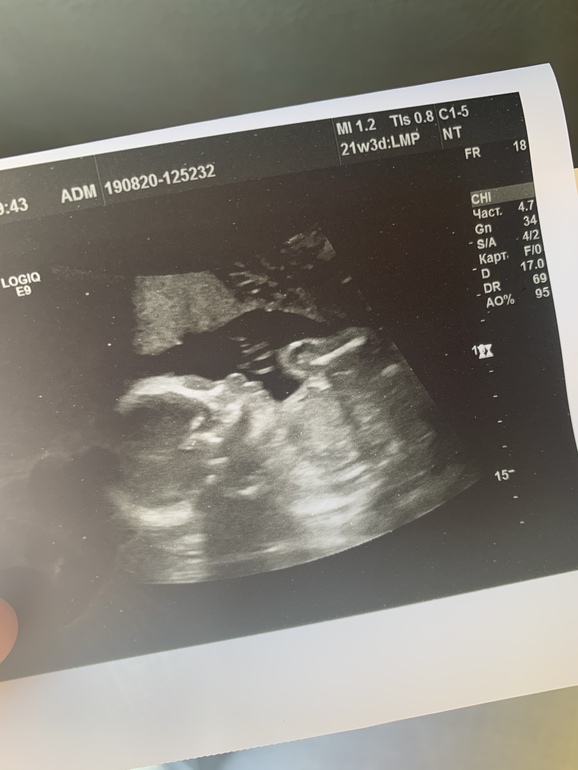

Сегодня была на «втором скрининге».

Узист сказала все в норме, но гипертонус🥺

И все таки подтвердили девчулю❤️